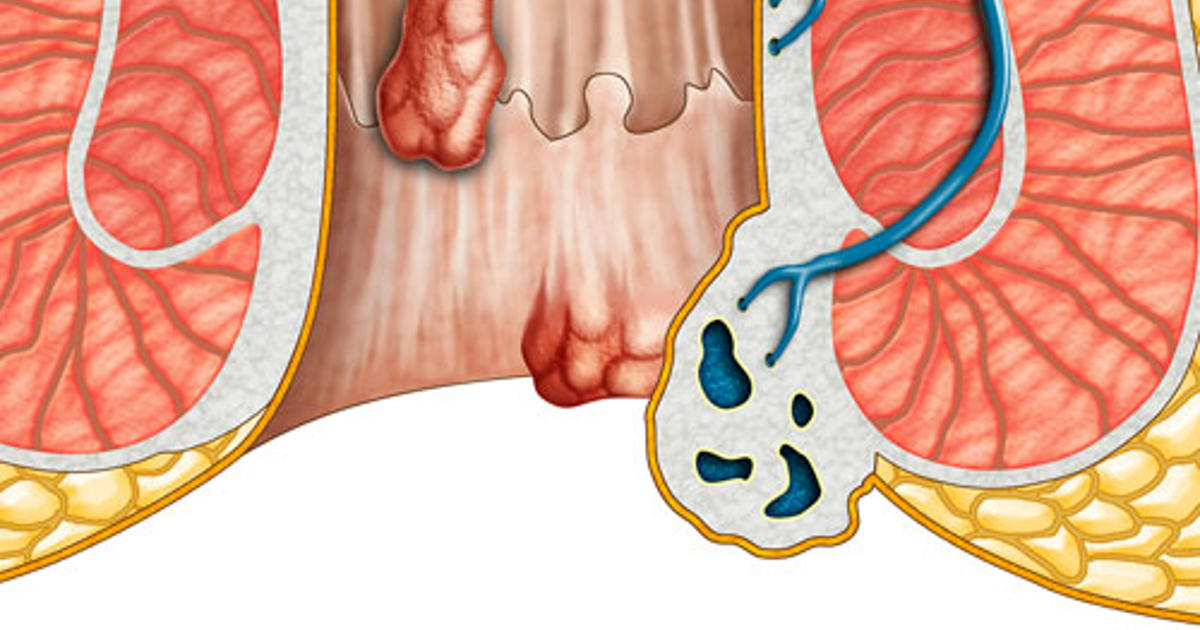

Οι αιμορροΐδες χωρίζονται σε δύο κύριες κατηγορίες, ανάλογα με το αν η φλεγμονή εντοπίζεται στο εσωτερικό ή το εξωτερικό τμήμα του πρωκτού:

- Εσωτερικές: Σχηματίζονται διογκωμένες φλέβες στο εσωτερικό του ορθού, οι οποίες δεν είναι ορατές. Οι εσωτερικές αιμορροΐδες εμφανίζουν ως βασικό σύμπτωμα την αιμορραγία, αλλά συνήθως δεν είναι επώδυνες.

- Εξωτερικές: Οι διογκωμένες φλέβες σχηματίζονται κάτω από το δέρμα γύρω από τον πρωκτό, και είναι ορατές στο μάτι. Οι εξωτερικές αιμορροΐδες μπορεί να είναι επώδυνες και να προκαλέσουν φαγούρα και αιμορραγία.

- Θρομβωμένες: Σχηματίζονται λόγω υπερβολικής συγκέντρωσης αίματος στον αιμορροϊδικό ιστό. Μπορούν να προκύψουν είτε στην περίπτωση των εσωτερικών ή των εξωτερικών αιμορροΐδων, αλλά συνήθως δημιουργούνται στις εξωτερικές, προκαλώντας πόνο, κνησμό, πρήξιμο και ερυθρότητα στην περιοχή. Χρειάζονται άμεση αντιμετώπιση προκειμένου να μην διακοπεί η παροχή αίματος προς τον πρωκτό ή το ορθό.